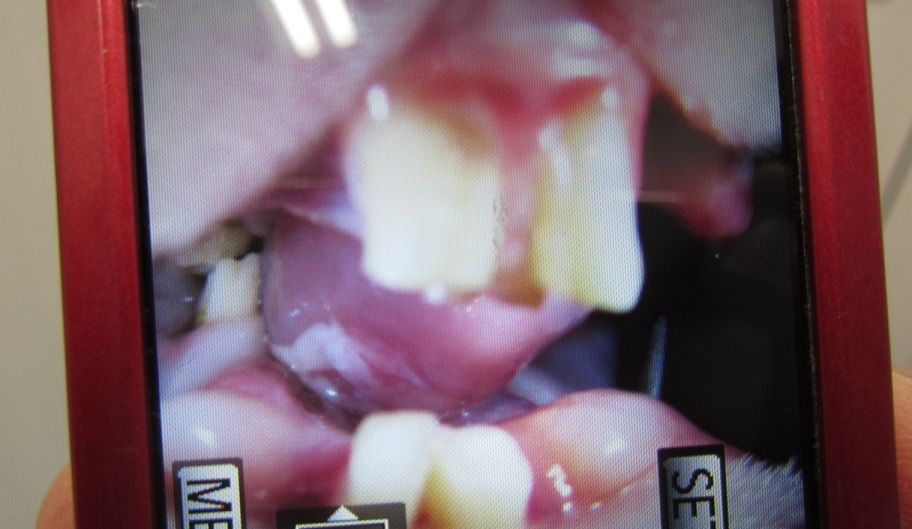

舌の傷もずいぶん良くなってきています。

向かって左側の白くなってるところ

1月7日の部屋んぽにて

画像で見るとすごく腫れてるように感じますね(;´Д`)

写真を撮りたかったのではなく、

口くちゃくちゃの動画を撮りたかったんですよ

奥歯いっぱいなくなったら、そら気になるよね…。